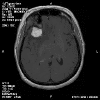

Clinical information The patient was a 54 year-old woman with a history of diabetes. She developed vomiting and frontal headache for two days. As per the descriptions of her family members, she had a few episodes of starring into the left and was unresponsive. The patient described that she could remember all these episodes clearly. On physical examination, the patient was well oriented and alert. There was no weakness in the extremities, ophthalmoplegia, diplopia, reduced visual acuity or facial weakness. An MRI and a CT scan were performed and yielded the following representative images. A surgery was performed. Representative photographs of the specimen are illustrated below.

T1-weighed MR images demonstrate an extraaxial, dural based mass involving the right supraorbital region  (Panel A and B). The mass shows homogeneous enhancement  (Panel C). CT scan demonstrates as well as rim calcification (Panel E). On T2-weighed imagers, significant vasogenic edema is demonstrated despite the small size of the lesion and the extraaxial location (Panel D).